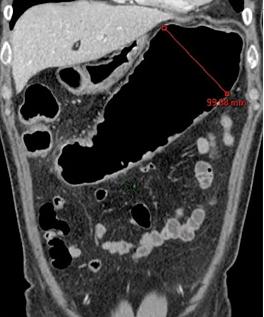

Aspect radiologique TDM

du megacolon . La colon transverse est tres dilate

en aerique . Image TDM en coupe coronal |

Meme cas

en coupe TDM sagitale . La portion innertie se

voyait longitudinal en arriere |